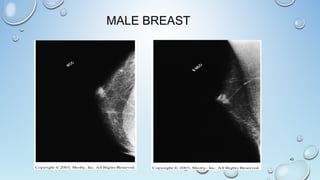

THE MALE BREAST

Male Mammography and Cancer

GYNECOMASTIA

• Benign Excessive Development Of Male Mammary Gland

• Occurs In 40% Of Male Cancer Pt’s

• Survival Rates With Treatment Are 97% For 5 Years

MALE BREAST

MALE MAMMOGRAPHY

• 1300 MEN GET BREAST CANCER PER YEAR

• 1/3 DIE

• MOST ARE 60 YEARS OR OLDER

• NEARLY ALL ARE PRIMARY TUMORS

• SYMPTOMS INCLUDE:

• NIPPLE RETRACTION

• CRUSTING

• DISCHARGE

• ULCERATION